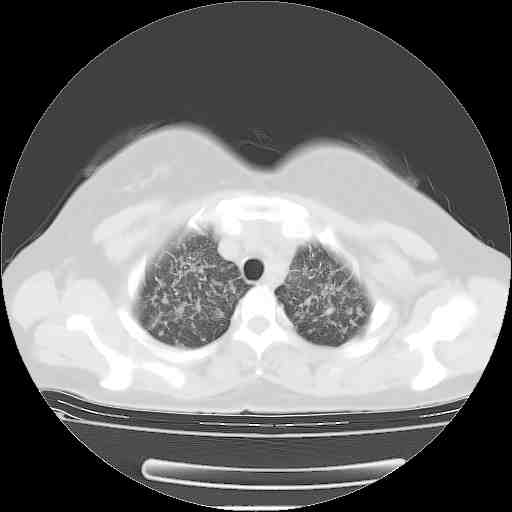

f50,肺ca治疗后,做过穿刺,确诊是肺ca,大家看看这是去年12月做的

考虑  腺癌肺内转移,治疗较前病灶缩小、减少

支持肺癌并肺内淋巴管转移,

支持肺癌并肺内淋巴管炎,  原发灶小了,但转移较前片明显了.

支气管血管束粗而乱,考虑肺癌肺内淋巴管转移,右侧乳房第一二层软组织成份较左侧多,不会有问题吧?

支持右肺下叶周围型肺癌并肺内淋巴管炎,  原发灶小了,但转移较前片明显了.。

标准的细支气管肺泡癌呀!治疗后病情有所控制,也没治愈的迹象!